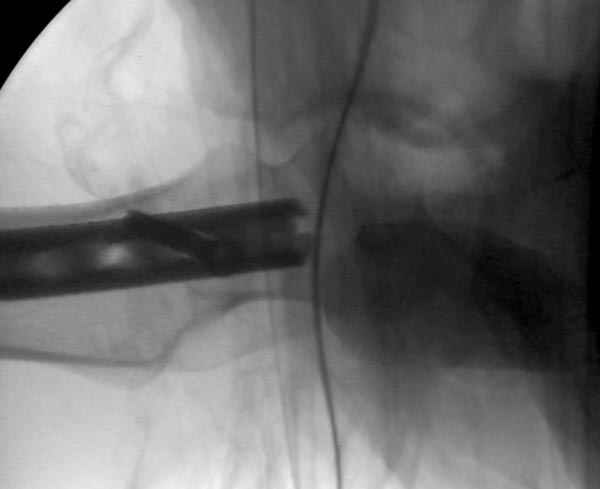

Как раз недавно у меня был примерный случай: больному 36 лет, поступил ночью, травма в результате мотоциклетной аварии, кроме чрезвертельного и спирального перелома левого бедра имеется переломы костей предплечья с этой же стороны. Скелетное вытяжение, а на следующий день больной про оперирован на ортопедическом столе с дистракцией. Чтобы не расколоть чрезвертельный перелом провели временную спицу ближе к переднему кортексу, из малого разреза костодержатель для репозиции, а фиксацию провели антиградным штифтом. Этапы операции на снимках.

DK> фиксацию провели антеградным штифтом.

Да, сейчас это и у нас самый напрашивающийся выбор. Сделали гвоздем ChM, картинки в приложении.